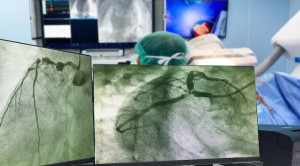

• Memahami Terapi Dual Antiplatelet setelah Percutaneous Coronary Intervention

Memahami Terapi Dual Antiplatelet setelah Percutaneous Coronary Intervention

Terapi dual antiplatelet sering digunakan pada pasien dengan penyakit jantung koroner (PJK) setelah tindakan kateterisasi jantung atau Percutaneous Coronary Intervention (PCI). Tujuannya adalah untuk...(Baca Selengkapnya)

• Percutaneous Coronary Intervention pada Sindrom Koroner Akut: Radial atau Femoral

Percutaneous Coronary Intervention pada Sindrom Koroner Akut: Radial atau Femoral

Percutaneous coronary intervention atau intervensi koroner perkutan pada sindrom koroner akut dapat dilakukan dengan pendekatan radial atau femoral. Masing-masing pendekatan ini mempunyai...(Baca Selengkapnya)